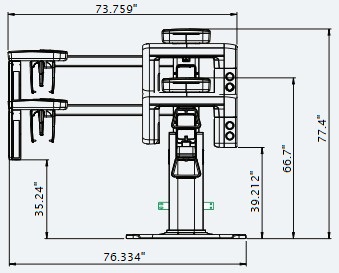

| Without CEPH unit | With CEPH unit | |

| FRONT VIEW |

|

|

*An additional 3 inches (76.2 mm) of space is required behind the unit for wall mount bracket installation

(mandatory unless there is a base mount installation).